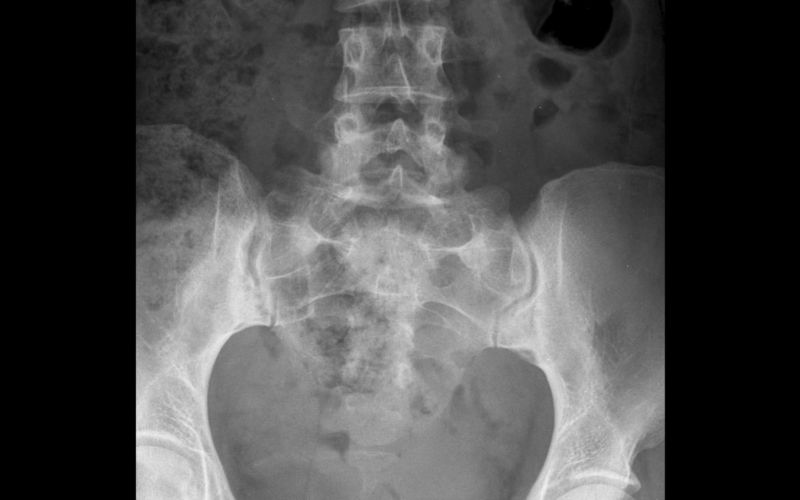

Diagnostic : clinique d’abord, imagerie si nécessaire

Le diagnostic est avant tout clinique : interrogatoire (déclencheurs, charges récentes, sports), tests fonctionnels (montée sur marche, appui unipodal, tests de résistance des abducteurs, mise en tension du psoas/TFL), palpation du grand trochanter.

L’échographie visualise l’inflammation, l’épaississement tendineux et une éventuelle bursite trochantérienne associée. L’IRM peut préciser les lésions en cas de doute ou d’échec thérapeutique.